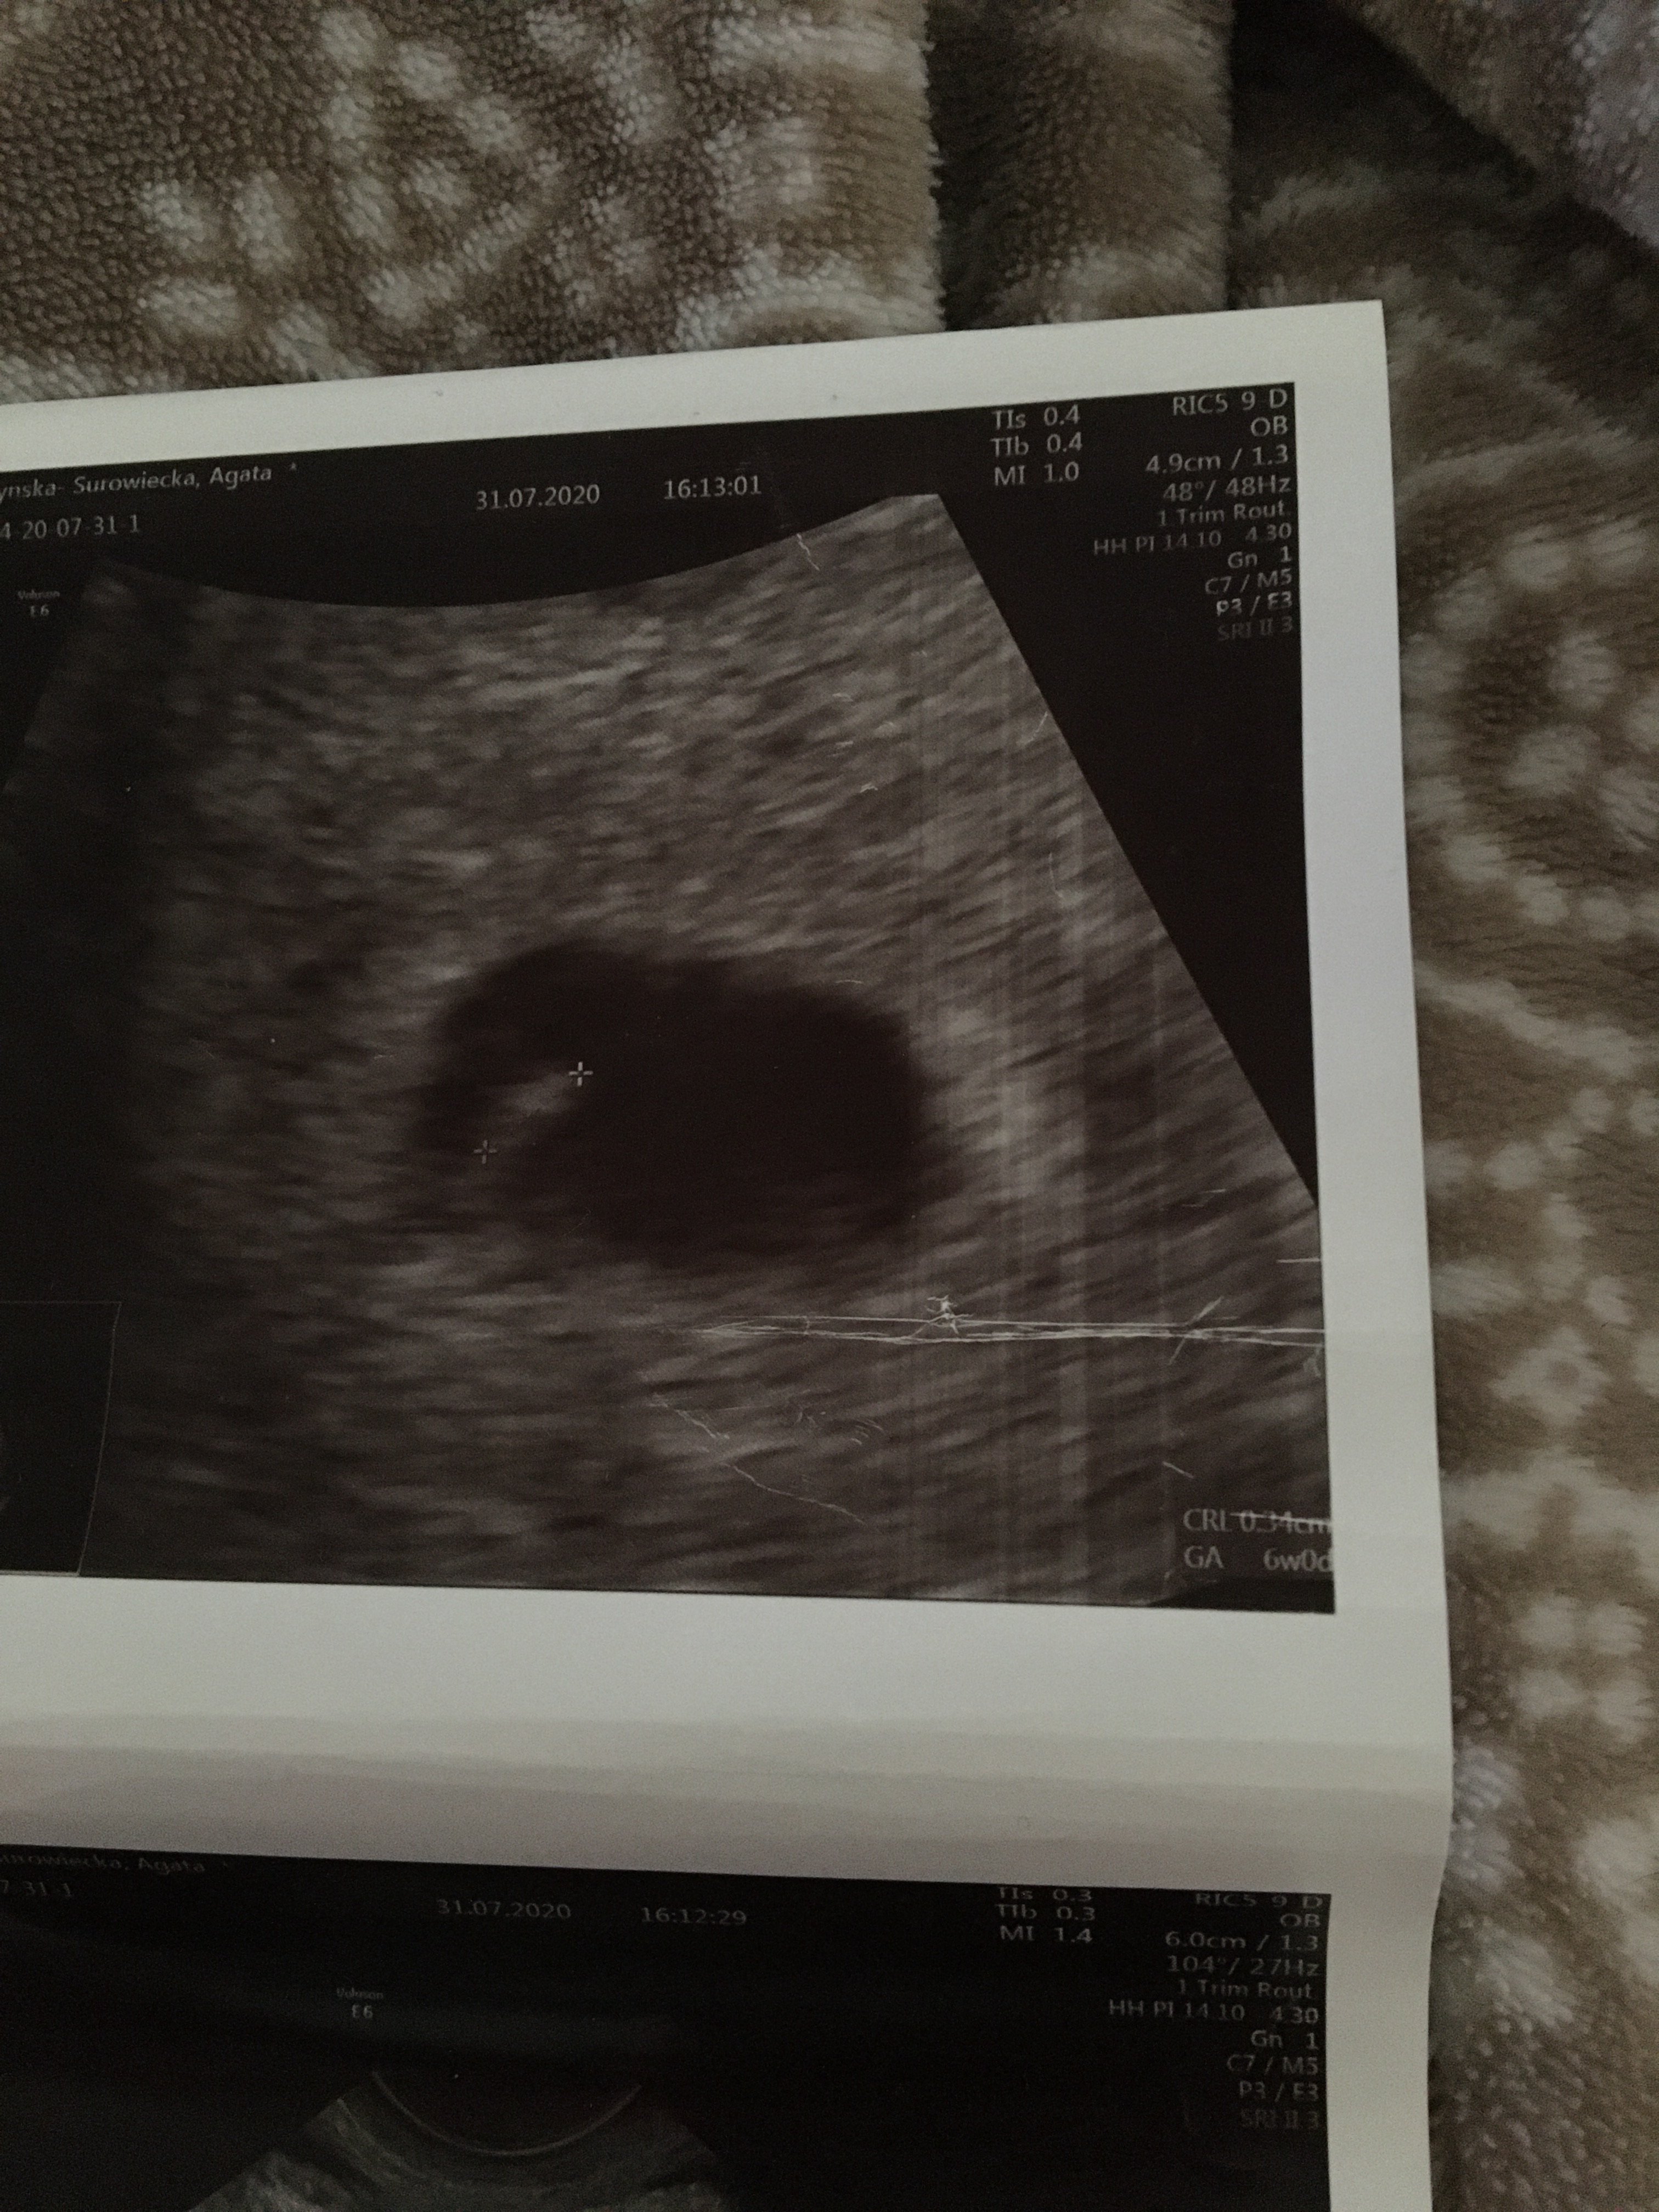

Dziewczyny z powodu plamienia trafiłam nagle do lekarza w piątek. Lekarz zrobił usg i według niego 6 tydz 1 dzień. Czy widać Tutajj zarodek ? Lekarz niestety mi tego nie wytłumaczył tylko pogratulował... czy powinnam się martwić ? Wiele z was pisze ze w 6 tygodniu słychać już serduszko

Tak, jest zarodek i ciałko żółte masz nawet wymiary podane na zdjęciach GS to pęcherzyk ciążowy, a CRL to wymiar zarodka:)